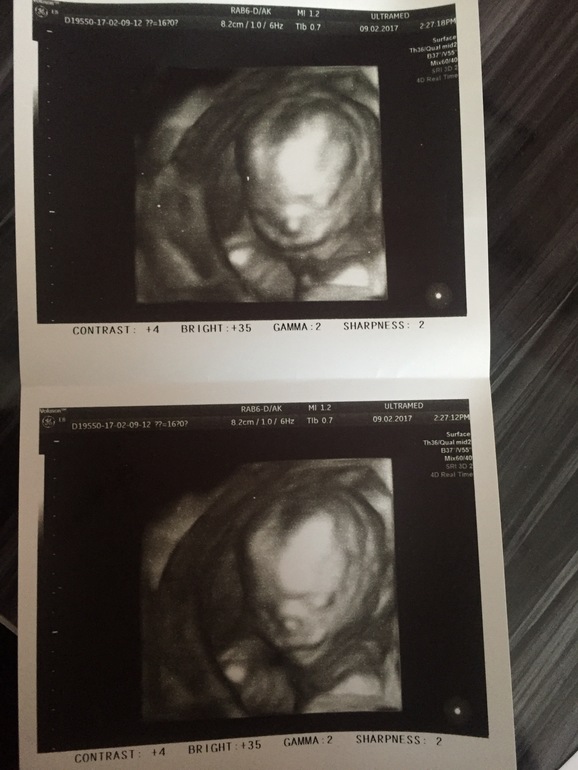

Сходили с мужем на внеплановое узи, посмотреть малыша, узнать пол) ииии у нас девчуля!) как мы о ней мечтали!!!))) именно ее и хотели!))) на узи она спала сначала, потом начала движуху наводить, даже сосала пальчики на ноге😄 СЛАдкая девочка наша)) муж прыгает до потолка)))